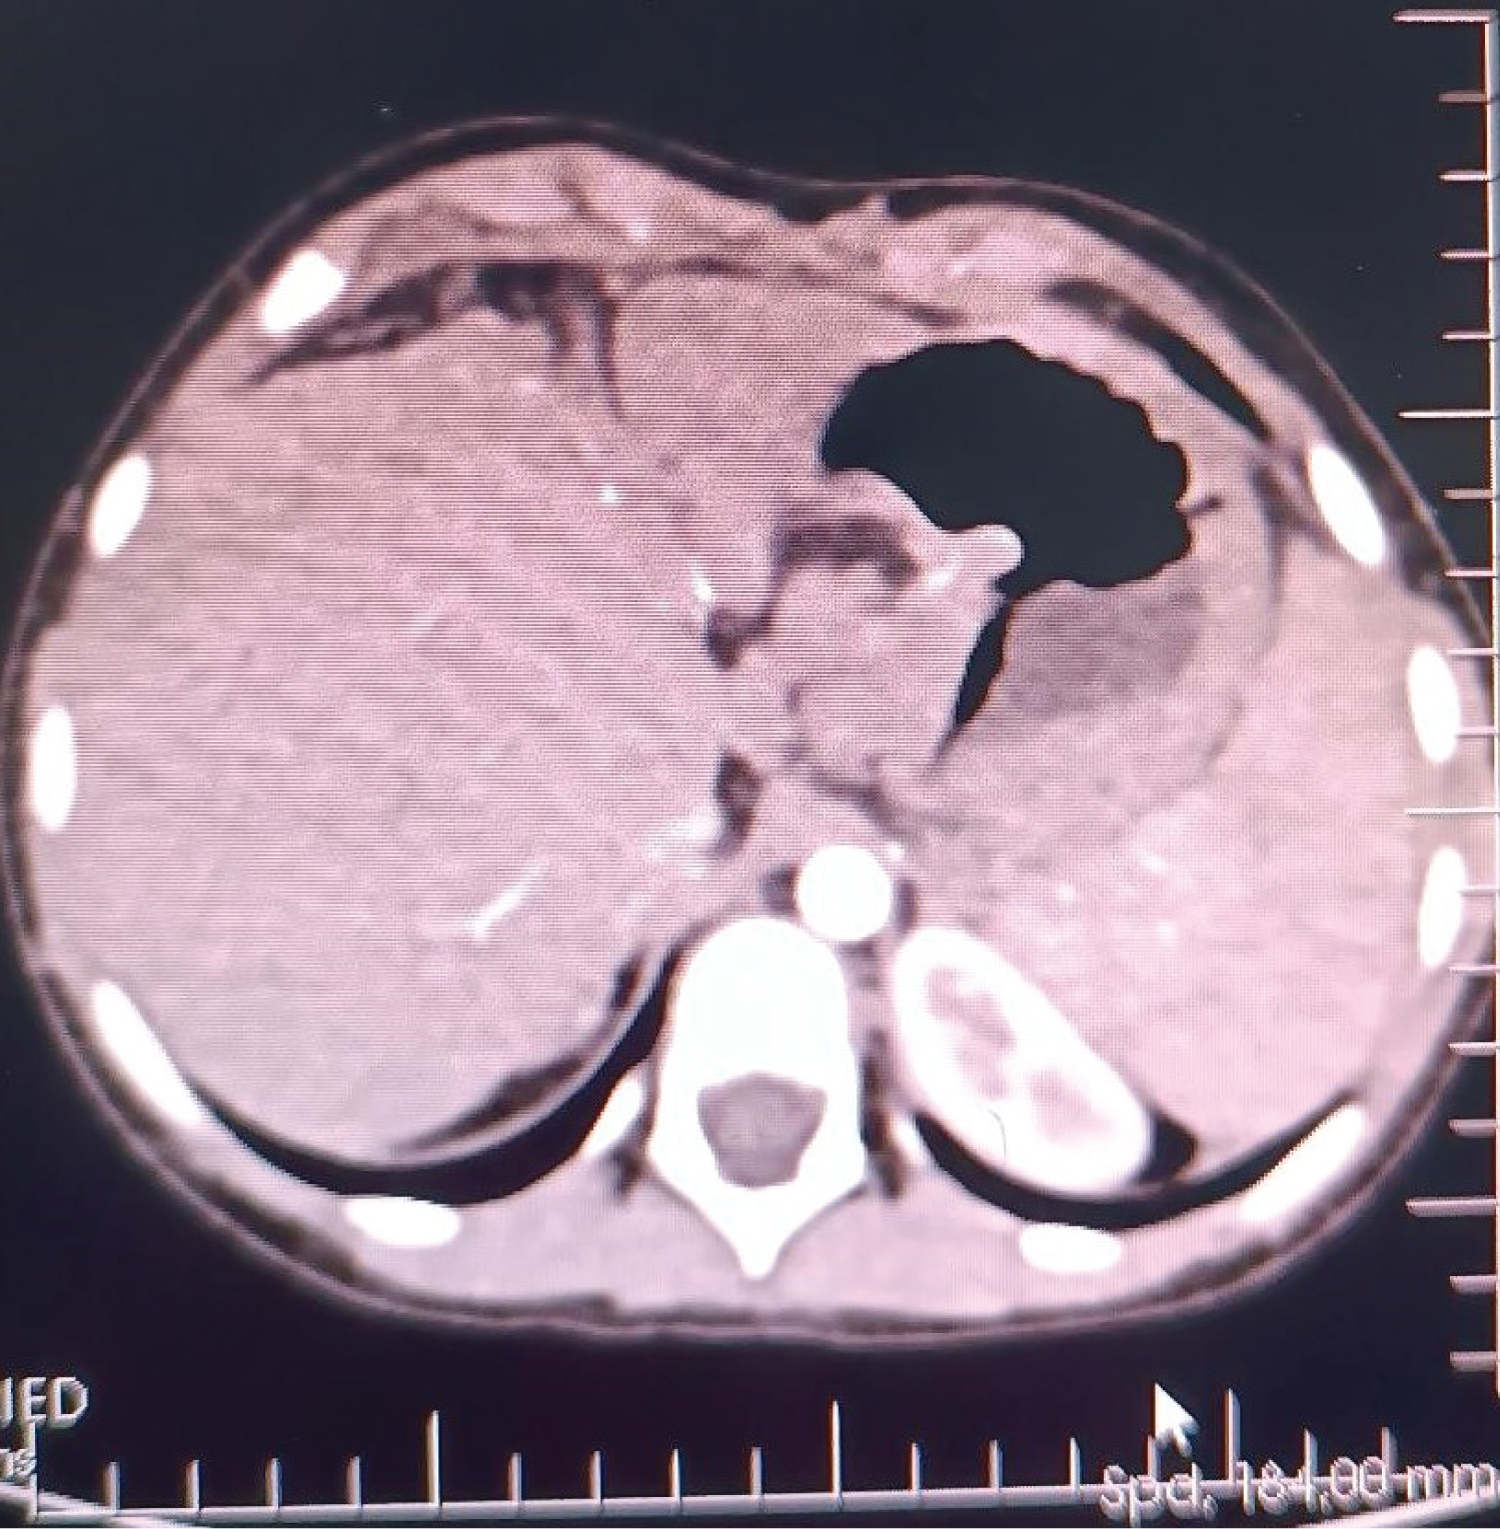

A 6-year-old female (height: 115 cm, weight: 22 kg) patient with pediatric living donor LT for biliary atresia (cirrhosis with portal hypertension) with a pulmonary AVF, HPS, was admitted to an intensive care unit (ICU) transplantation. She had a Kasai operation on the 45 th day after birth to treat biliary atresia. After the Kasai procedure, the patient developed malnutrition due to portal hypertension, hepatosplenomegaly, jaundice, ascites, and esophageal varices. After month 5, dyspnea, platypnea, orthodeoxia, weakness, cyanosis when crying, clubbing, and cyanotic fingertips began to appear. These findings' presence in ESLD patients made us think of HPS, and CE-TTE was then performed, and microbubbles were observed in the left atrium on CE-TTE. A lung perfusion scan revealed an intrapulmonary right-to-left shunt fraction of 25%, and pulmonary arteriography was also diffuse IPVD and pulmonary AVF without capillary phase was detected. In the patient's liver computed tomography (CT)-angiography, diffuse hepatoportal shunt and splenomegaly were found in the liver parenchyma due to the operated biliary atresia (Figure 1). She later developed cirrhosis and was followed up with a diagnosis of cirrhosis until the age of 6 years.

Figure 1: In the patient's liver computed tomography (CT) - angiography, diffuse hepatoportal shunt and splenomegaly were found in the liver parenchyma due to the operated biliary atresia.